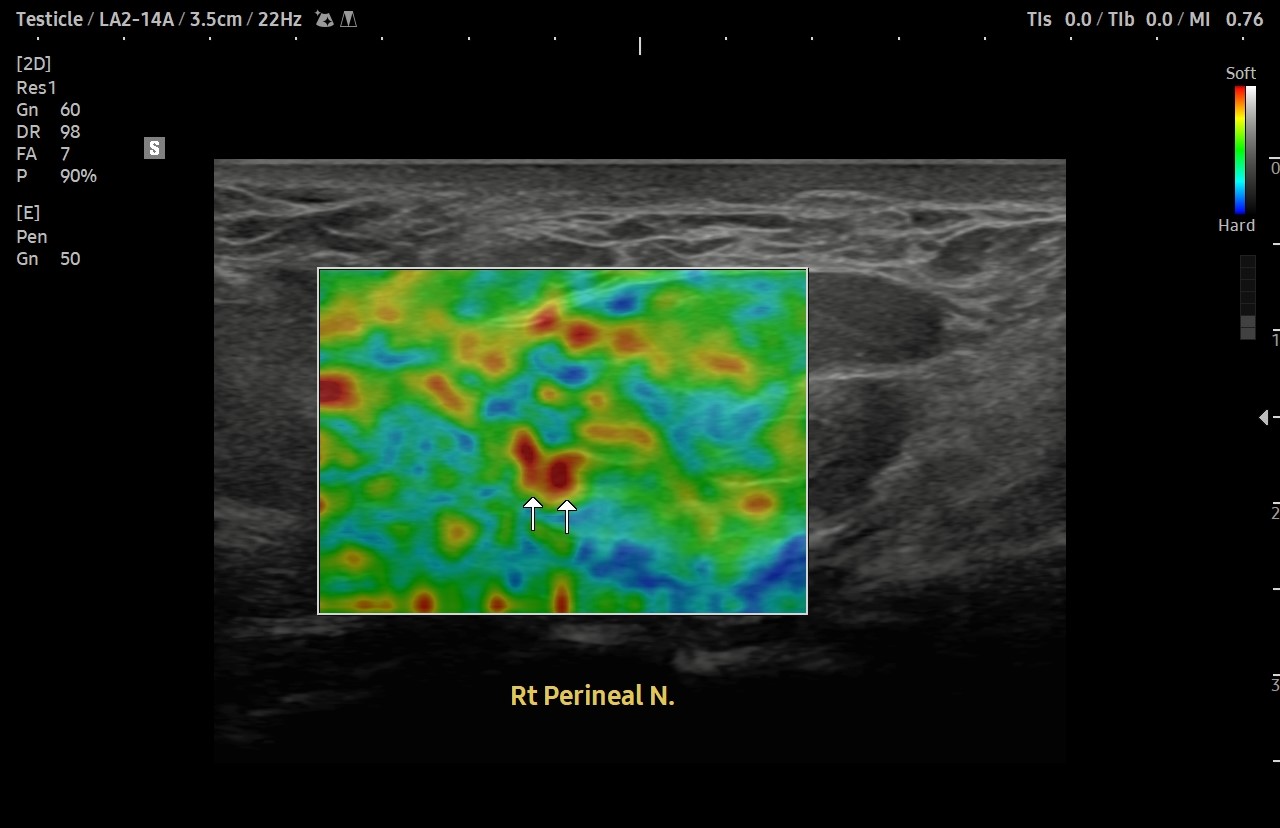

[치료 전]

[치료 후]

- 치료횟수 : 58 회